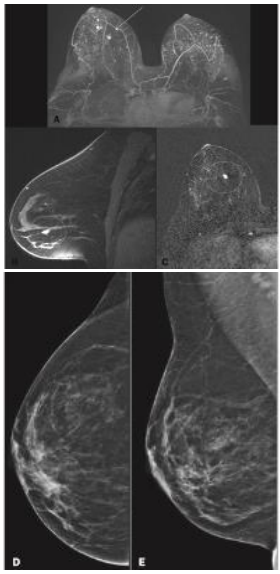

Paciente de 42 anos realizou mamografia e RM para rastreamento de câncer de mama.

Em relação ao rastreamento de câncer de mama, assinale a afirmativa correta.